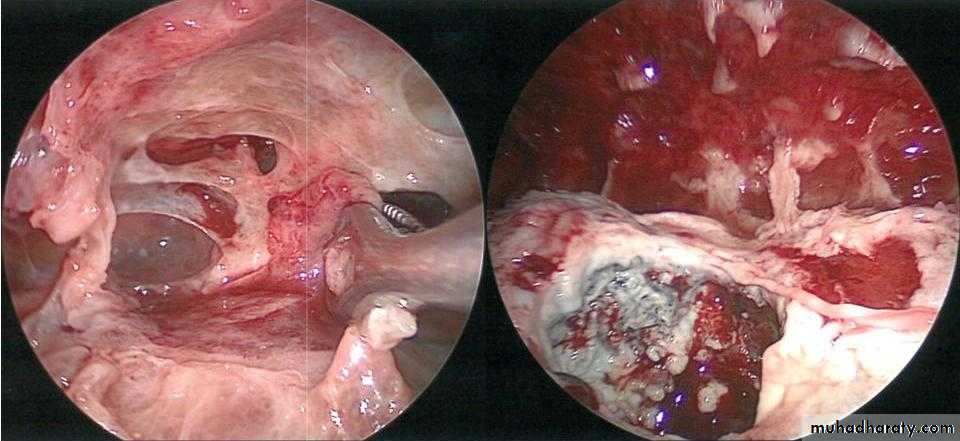

4- VATS or Thoracotomy : decortications with pleurectomy

• Bronchoscopy : To exclude or confirm Ca

• To diagnose and remove foreign bodies

• To drain an abscess

• To obtain a bronchial wash for C/S